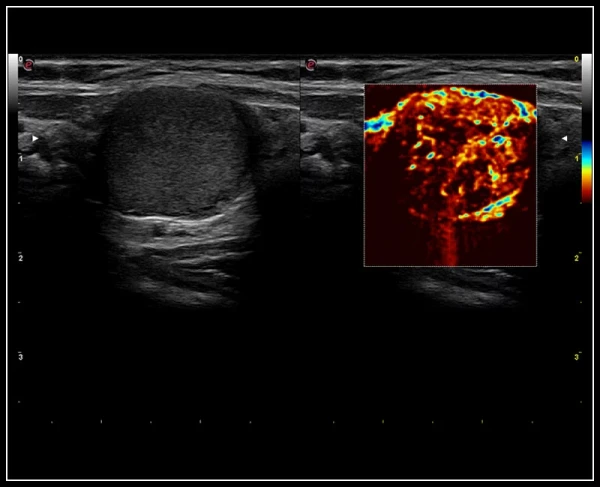

ULTRA-Color Doppler rangli xaritalash usullari: yuqori sezuvchanlik, chuqur kirish va yuqori aniqlik

QPack. Doppler rejimlarida va CnTI kontrastli tasvirlash texnologiyasidan foydalangan holda kontrast agenti perfuziyasini miqdoriy baholash uchun yangi vosita